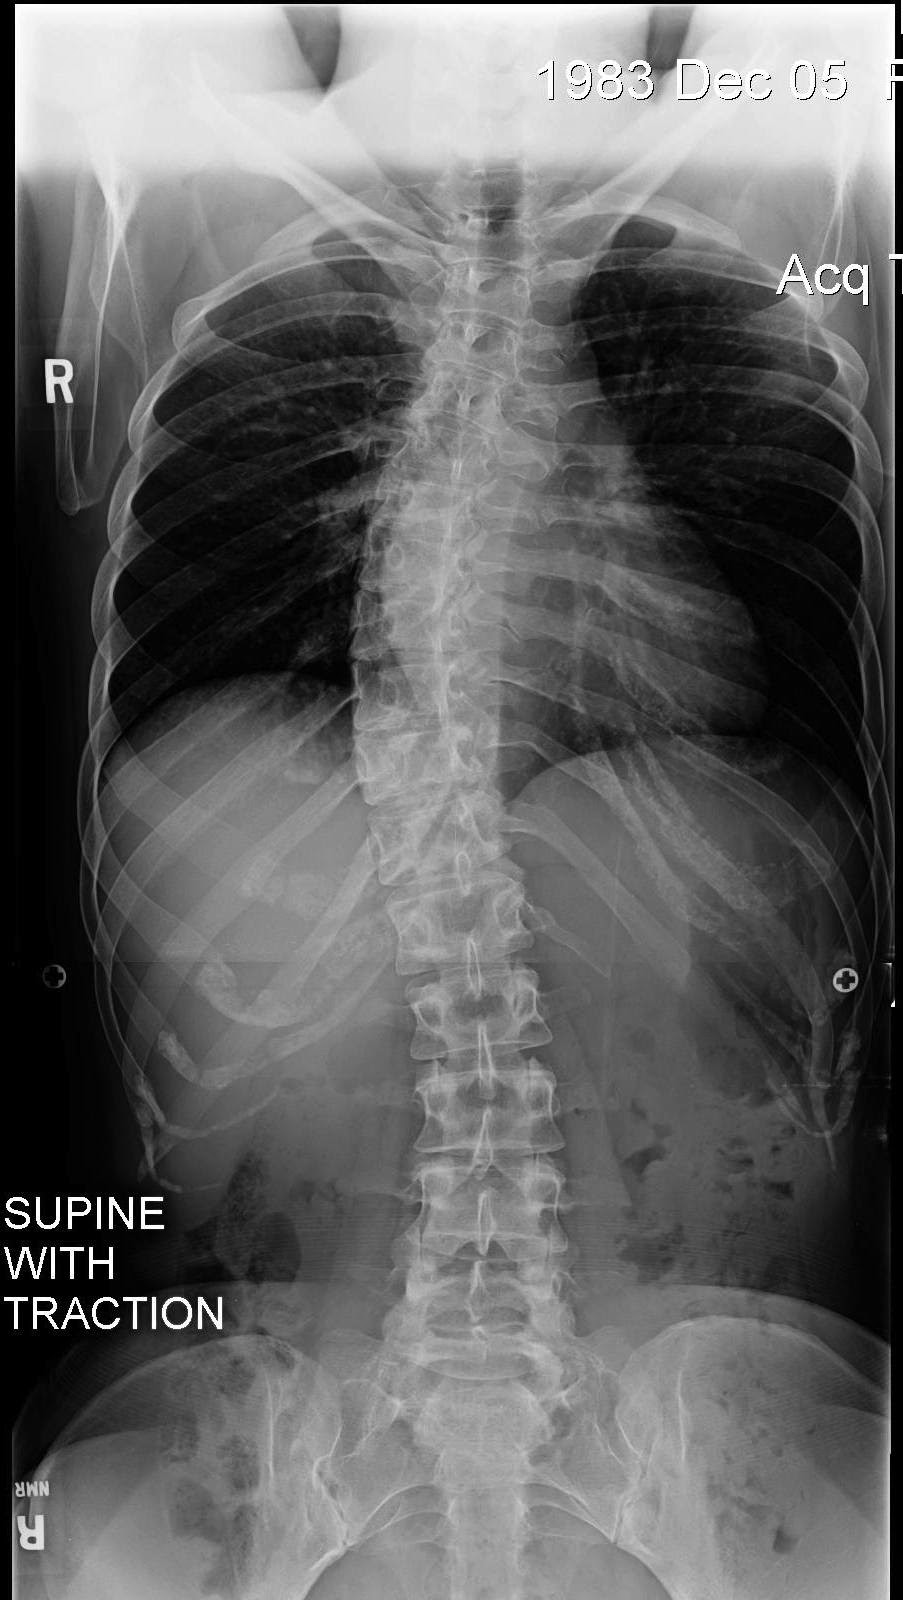

and an X-ray with two people pulling my arms and legs at both ends!